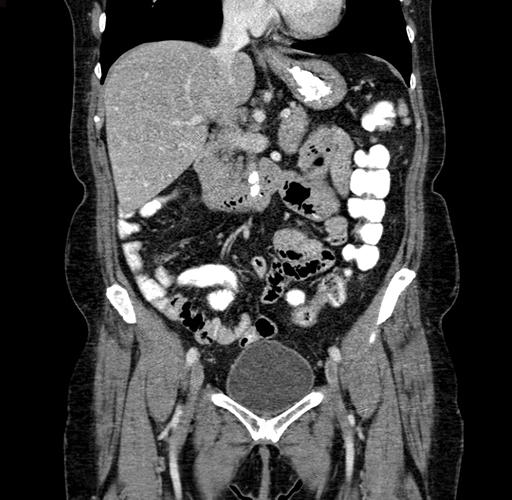

Pre-Chemo: Coronal Venous